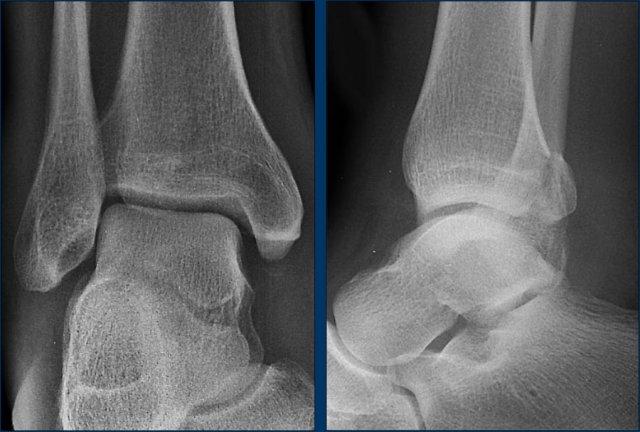

case 5 – chronic pain

The findings are:

- narrowing of the posterior subtalar joint with sclerosis

- C sign

Khớp dưới sên bao gồm các diện khớp trước, giữa và sau. Hợp khối xương sên-gót thường gặp nhất ở diện khớp giữa tại mức độ của mỏm chống sên.

Hợp khối xương sên-gót có thể khó quan sát trên các tư thế chụp X-quang tiêu chuẩn của bàn chân do hướng phức tạp của khớp dưới sên.

Một số dấu hiệu X-quang thứ phát của liên hợp xương sên-gót đã được mô tả, bao gồm:

- Talar beak

- Narrowing of the posterior subtalar joint

- Rounding of the lateral talar process

- Thiếu hình ảnh mô tả các diện khớp giữa trên phim X-quang thẳng.

- C-sign

Mỏ xương sên xảy ra do sự suy giảm chuyển động của khớp dưới sên, dẫn đến xương thuyền trượt lên trên xương sên. Sự nâng màng xương xảy ra tại điểm bám của dây chằng sên-thuyền, và cuối cùng, một chu kỳ sửa chữa xương dẫn đến sự hình thành mỏ xương sên.

Dấu hiệu “C” là một đường hình chữ C trên phim chụp nghiêng, phác thảo vòm xương sên phía trong và xương chêm sau dưới. Dấu hiệu C xuất hiện do sự cầu nối xương giữa vòm xương sên và xương chêm, cũng như đường viền dưới nổi bật của xương chêm.

Khi chùm tia X chiếu tiếp tuyến với đường viền sau dưới của xương chêm bất thường trên một khoảng cách dài, một hình chữ “C” liên tục được tạo thành. Dấu hiệu C có thể được quan sát thấy trong cả các liên kết xương và không xương.